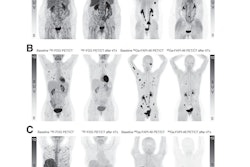

The study included 17 patients who underwent three PET/CT scans of the kidneys and areas where tumors manifest. The patients were intravenously administered an average dose of 5.7 GBq. The researchers also derived lesion and kidney uptakes from PET/CT scans taken one, four, and 20 hours postinjection, respectively.

Lesion uptake from a patient with a solitary fibrous tumor and its FAP expression on gallium-68 (GA-68)-FAPI-46 (A) and intratherpeutic Y-90-FAPI-46 (B). The panel shows the constructed time activity curve with the three PET/CT measurements.SNMMI

Of the total patients, 15 had sarcoma, one had prostate cancer, and one had gastric cancer. The study analyzed 31 primary and metastatic lesions located in the following areas: lung, pancreas, pleura, liver, thyroid, bone, and lymph nodes.

Costa reported that the average absorbed dose coefficient was 3.07 Gy/GBq, 0.38 Gy/GBq, and 0.04 Gy/GBq for the lesions, kidneys, and bone marrow. He also said the effective half-lives were 8.3 hours and 11.9 hours for lesions and kidneys.

Finally, the team found that bone marrow kinetics were characterized by a “very fast” initial decay of 0.4 hours followed by a dominant phase with an effective half-life of 7.5 hours.